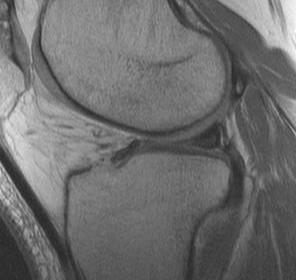

MRI Classification

Stoller 1987 J. Radiol.

Grade 0

- normal homogeneous low signal intensity

Grade I

- globular increase signal in meniscus

- doesn't reach either surface

Grade II

- linear increase signal, doesn't reach surface

- myxoid intra-meniscal degeneration / partially healed tear

Grade III

- increased signal intensity communicates with meniscal surface

- 70-90% accurate for true tear

- accuracy MM > LM

MRI Pitfalls / Normal Findings or Variants

Ligaments of Wrisberg PMFL & Humphrey AMFL

Transverse Anterior Meniscal Ligament

Signs of bucket handle tear meniscus

1. Double PCL sign

- medial Meniscus

2. Absent bow tie sign

- should see bow tie image on 2 consecutive sagittal slices of 5 mm

3. Fragment in notch sign

4. Anterior flipped meniscal sign

- torn fragment flips over the anterior horn of the affected meniscus

5. Truncated meniscus